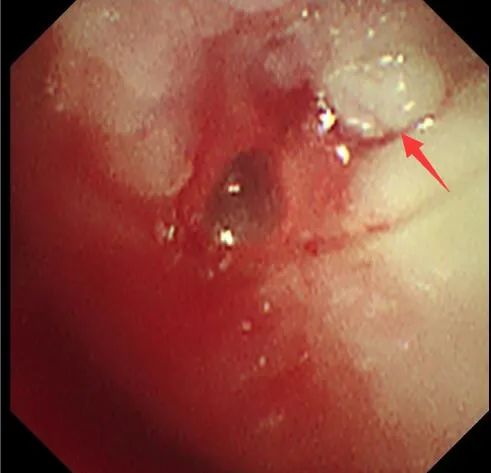

支架置入前(图 1 为 CT 冠状位,红色箭头提示肿物阻塞气道;图 2 为 CT 纵隔窗,白色箭头所指为气道肿物;图 3 为气管镜下图像,红色箭头所指为气道肿物。)

手术团队果断进行电圈套器套切肿瘤、止血治疗,经处理后管腔明显通畅,镜下见气道肿瘤浸润范围从气管下段一直到隆突,右主气管管腔中度狭窄,呼吸介入团队在导丝引导下成功置入 Y 型覆膜支架。术后患者呼吸困难症状明显改善,欣喜的同时也感受到了自由呼吸的来之不易。